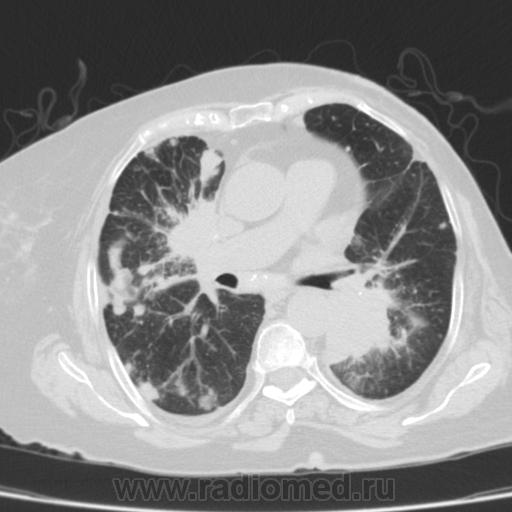

Метастатическое поражение легких.

Пожилая женщина, 76 лет находится на стац.лечении, провели СКТ дообследование.  Сопут- сr левой молочной железы. Такие множественные

поражения  в легких встречаются не часто.

Раннее несколько лет назад оперирована по поводу рака левой молочной железы.